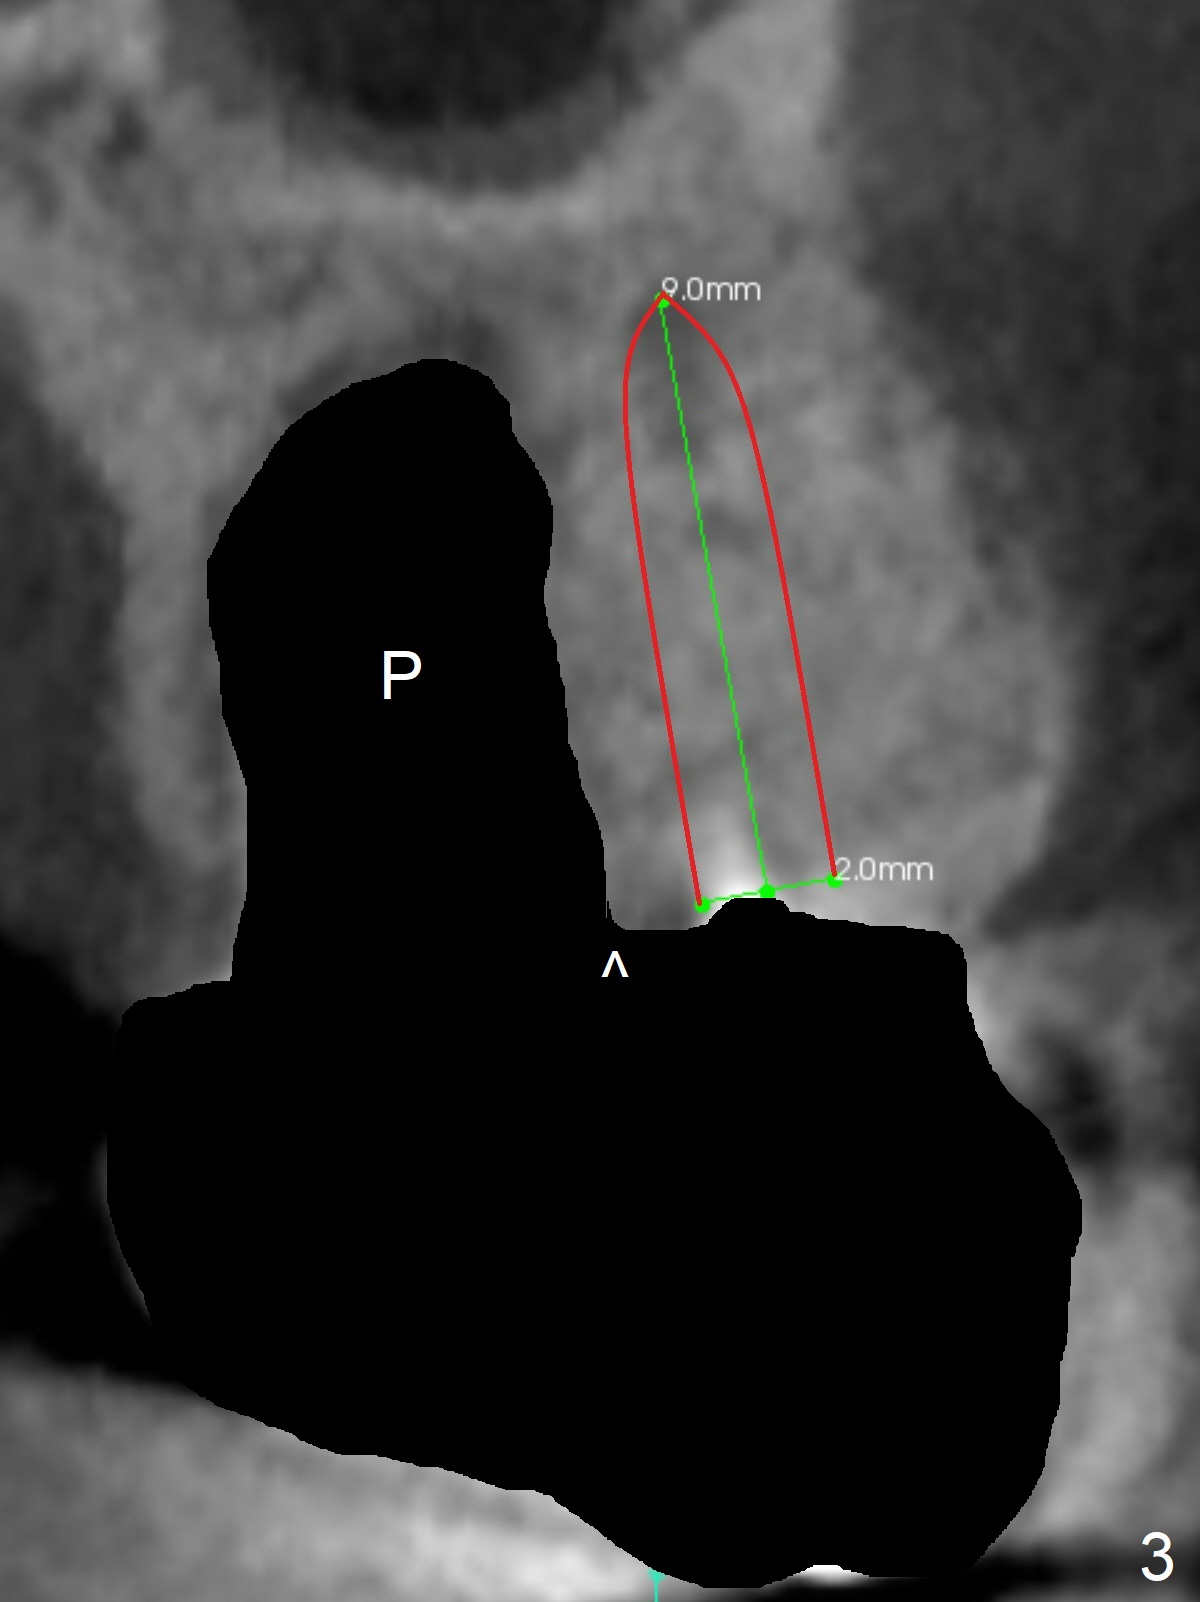

A 53-year-old man cannot chew on the left side with distal abscess in spite of RCT for #14 (* in Fig.1,2 (taken 11 ad 21 months postop, respectively)). After extraction (Fig.3 (CBCT coronal section) black area), start osteotomy with 2 mm drill (red outline) in the septum buccal to the palatal (P) socket). Following 2 mm drill removal (Fig.4), use 4.3 mm Magic Drill (red outline) for ~ 9 mm. When the osteotomy is being done, the osteotomy most likely shifts palatal (Fig.5 arrow) because of thin bone palatally. When the MD is removed (Fig.6), use Magic Sinus Lifter (Fig.7 pink) for sinus lift (arrow). The implant is to be 5x11 mm or larger. Because of the distal defect (Fig.1,2), start osteotomy mesially. Take Alginate impression before surgery for possible orthodontic treatment. Since bone density is high, use higher voltage and longer time for X-ray.